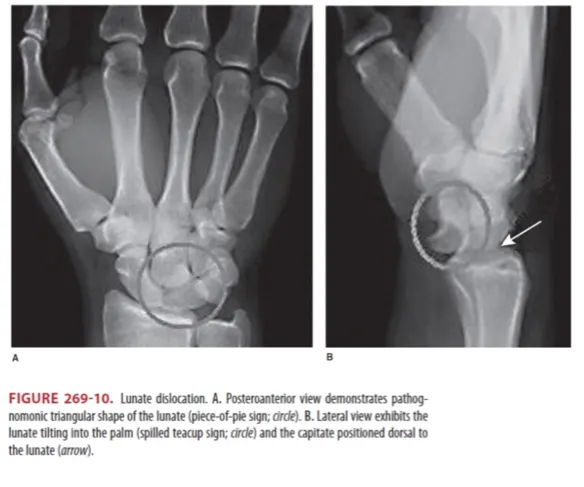

(2) Lunate dislocation

① Lunate가 radius에서 멀어지고 palm 쪽으로 위치하게 되는, ‘spilled teacup sign’이 보인다 (Figure 269-10B).